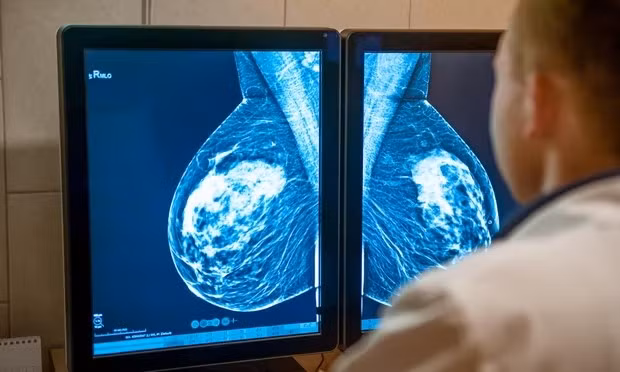

Nghiên cứu toàn cầu do AstraZeneca phối hợp với Viện nghiên cứu ung thư tại London, Quỹ tín thác NHS Royal Marsden và Viện Curie ở Paris (Pháp) thực hiện cho thấy bệnh nhân ung thư vú giai đoạn tiến triển có thụ thể hormone dương tính (HR+), thụ thể yếu tố tăng trưởng biểu bì ở người 2 âm tính (HER2-) được sử dụng Camizestrant kết hợp chất ức chế CDK4/6 đã làm giảm 56% nguy cơ ung thư phát triển.

Phương pháp xét nghiệm máu cải tiến trong thử nghiệm thuốc mới đã được sử dụng, được gọi là sinh thiết lỏng hay xét nghiệm ADN khối u lưu thông (ctDNA), để phát hiện ADN khối u và xác định những bệnh nhân có nguy cơ cao bị khối u đột biến trước khi có thể phát hiện khối u trên máy quét. Xét nghiệm này cho phép bệnh nhân được điều trị bằng loại thuốc mới ở giai đoạn sớm hơn.

Thuốc thử nghiệm Camizestrant đã ngăn không cho estrogen bám vào các tế bào ung thư và phá hủy các thụ thể của tế bào, khiến chúng khó kháng lại các liệu pháp điều trị hơn-AstraZeneca thông tin thêm.

Kết quả cho thấy ở những bệnh nhân dùng thuốc mới kết hợp với phương pháp điều trị hiện tại bệnh đã diễn tiến chậm lại trung bình 16 tháng, so với 9,2 tháng ở nhóm chỉ dùng phương pháp điều trị hiện tại.

Thử nghiệm cũng phát hiện ra rằng việc điều trị bằng loại thuốc mới giúp bệnh nhân có chất lượng cuộc sống tốt hơn trong thời gian dài hơn đáng kể so với tiêu chuẩn hiện tại.

Các chuyên gia kỳ vọng phát hiện này có thể mở ra chiến lược điều trị mới cho những bệnh nhân mắc loại ung thư phổ biến này. Các phát hiện từ thử nghiệm đã được công bố đồng thời trên Tạp chí Y học New England.